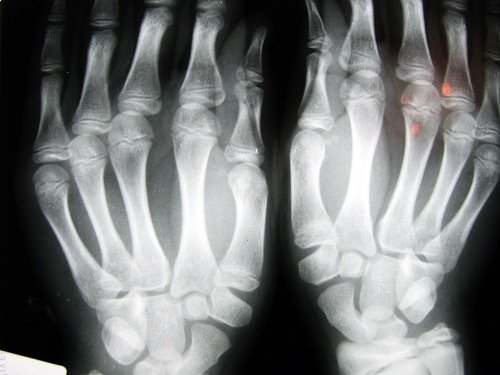

هشاشة العظام هو مرض عظمي يسبب انخفاض في كثافة العظام. ومن خلال زيادة حجم الخلايا الداخلية للعظام، تصبح هشة ومعرضة للكسر بسهولة أكبر.

تحدث الكسور عادةً لدى الأشخاص الذين يعانون من هذه الحالة في المعصم وفي عظم الورك أيضًا، وهو من أخطر أنواع الكسور لأنه يقتضي التدخل الجراحي الفوري، كما تكون عواقبه خطيرة على صحة المريض.